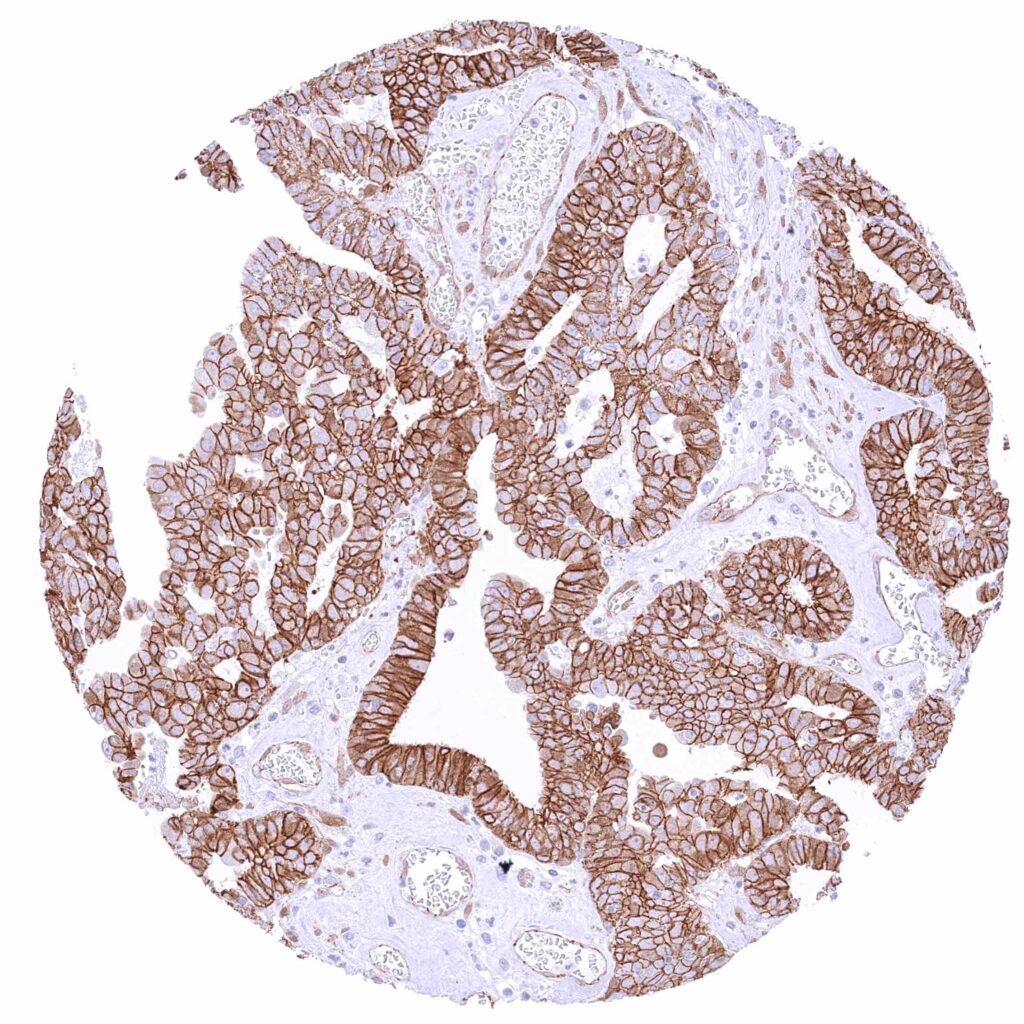

Ovary – Serous high-grade carcinoma with strong membranous β-Catenin immunostaining of tumor cells.

Ovary – Serous high-grade carcinoma with strong membranous β-Catenin staining of tumor cells.